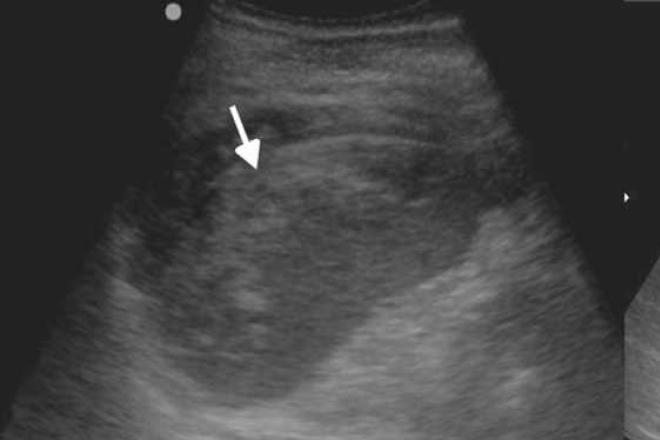

Cirrosis Hepática La cirrosis hepática suele asociarse al consumo de alcohol; sin embargo, como se verá en este artículo, la etiología de esta enfermedad es muy variada, al igual que las complicaciones que puede generar si no es diagnosticada a tiempo, con consecuencias para la